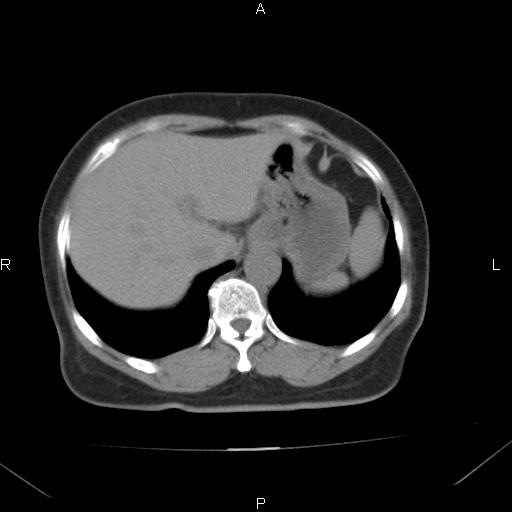

胸腺瘤

女、63Y 双眼睑下垂,早轻晚重。 胸腺瘤???

结果胸腺瘤